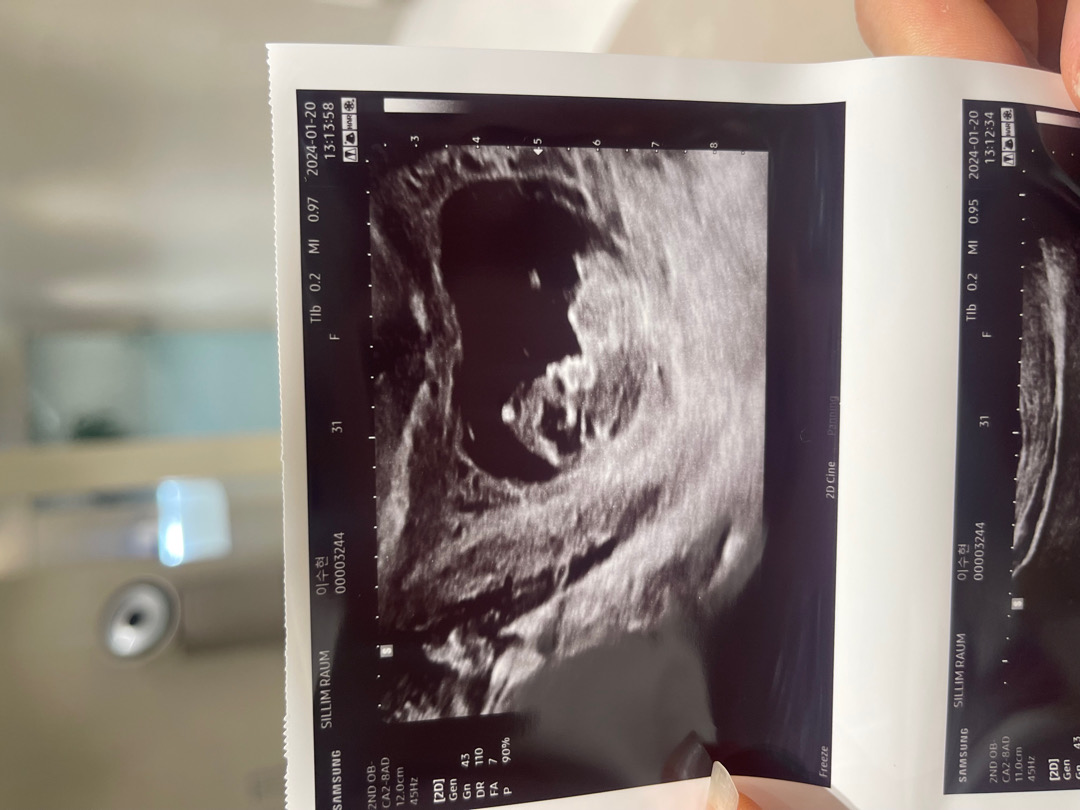

10주차 옆모습이에요 ㅎㅎㅎ!! 각도법 정확하진 않지만 너무 궁금하기도하구 재미로 한번 ,,,, 어떻게 보이시나요???